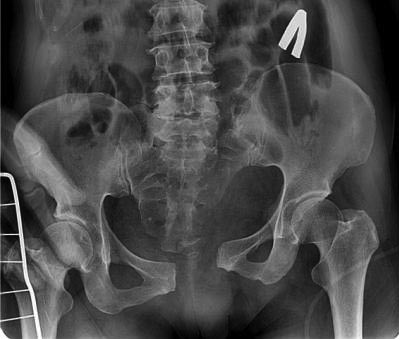

В данной ситуации повреждение тазового кольца типа С.

При разрыве КПС фиксация переднего полукольца порочна, вы "расхлопнули" заднее полукольцо.

На КТ видно перелом верхней и нижней ветви лонной кости